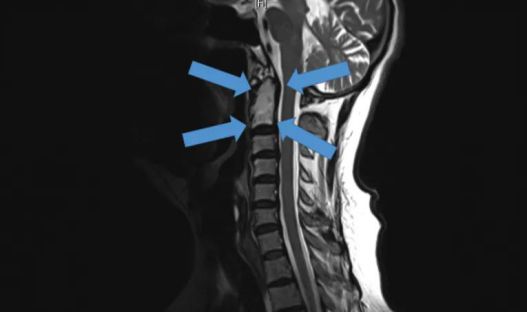

△2015年底,世界首例采用3D打印椎骨植入物

脊柱行業也是未來醫療器械市場,最新發展趨勢之一。通過3D打印技術,來達到創新產品的目的,該技術可以促進骨骼向內生長,并改善植入物對脊柱骨的固定,縮短制造流程,提高患者滿意度,從而在某些情況下更具成本效益。

例如,Medtronic鈦金屬3D打印平臺——TiONIC技術。使用激光方法制造具有增強表面紋理的植入物。Artic-L是該公司使用TiONIC技術制造的第一款金屬植入物??晒┩饪漆t生在脊柱手術中使用。還有K2M的Lamellar,同樣采用鈦制造3D脊柱植入物。使用金屬3D打印技術特有的優勢之一,可實現曾經被傳統制造技術,認為不切實際的結構。